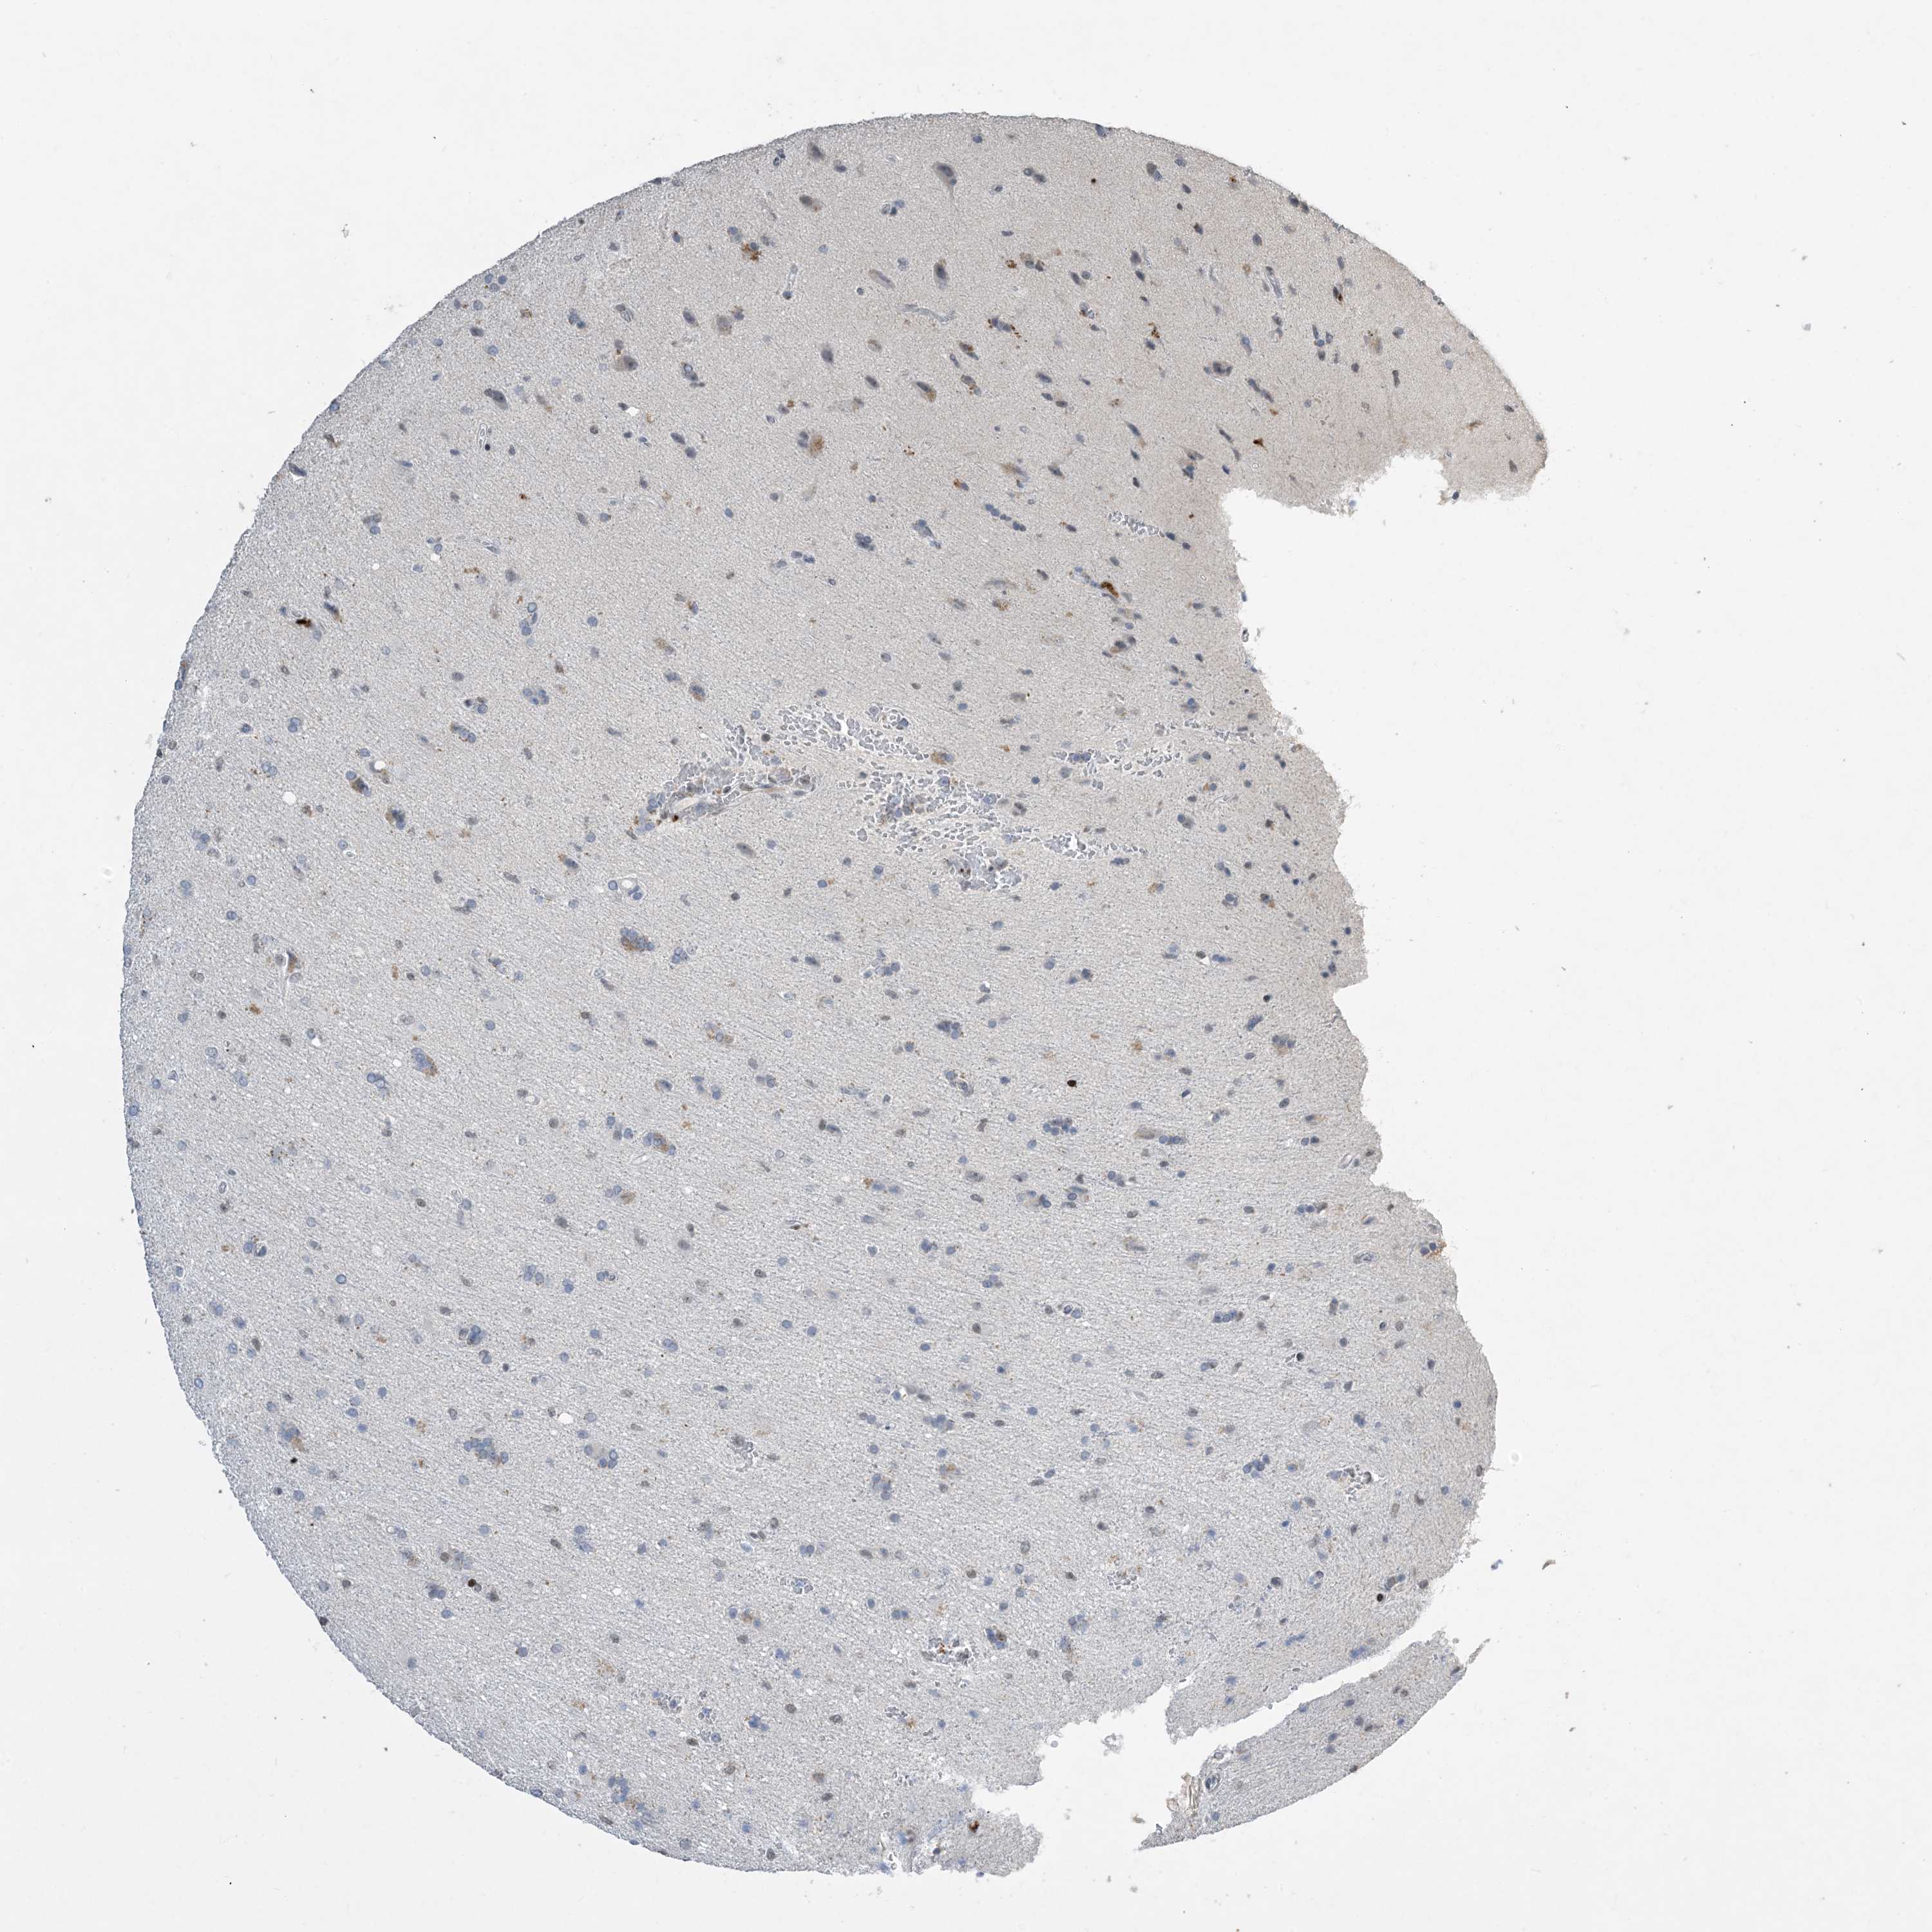

GLIOMA - Protein expressioni

A mouse-over function shows sample information and annotation data. Click on an image to view it in a full screen mode. Samples can be filtered based on level of antibody staining by selecting one or several of the following categories: high, medium, low and not detected. The assay and annotation is described here.

Note that samples used for immunohistochemistry by the Human Protein Atlas do not correspond to samples in the TCGA dataset.

Antibody stainingi

Antibody staining in the annotated cell types in the current human tissue is reported as not detected, low, medium, or high, based on conventional immunohistochemistry profiling in selected tissues. This score is based on the combination of the staining intensity and fraction of stained cells.

Each image is clickable and will lead to virtual microscopy that enables deeper exploration of all samples and also displays staining intensity scores, fraction scores and subcellular localization as well as patient and tissue information for each sample.

Antibody HPA034959

Staining

High

Medium

Low

Not detected

Intensity

Strong

Moderate

Weak

Negative

Quantity

>75%

75%-25%

<25%

None

Location

Nuclear

Cytoplasmic/membranous

Cytoplasmic/membranous,nuclear

Glioma, malignant, High grade

Glioma, malignant, Low grade

Glioblastoma, NOS